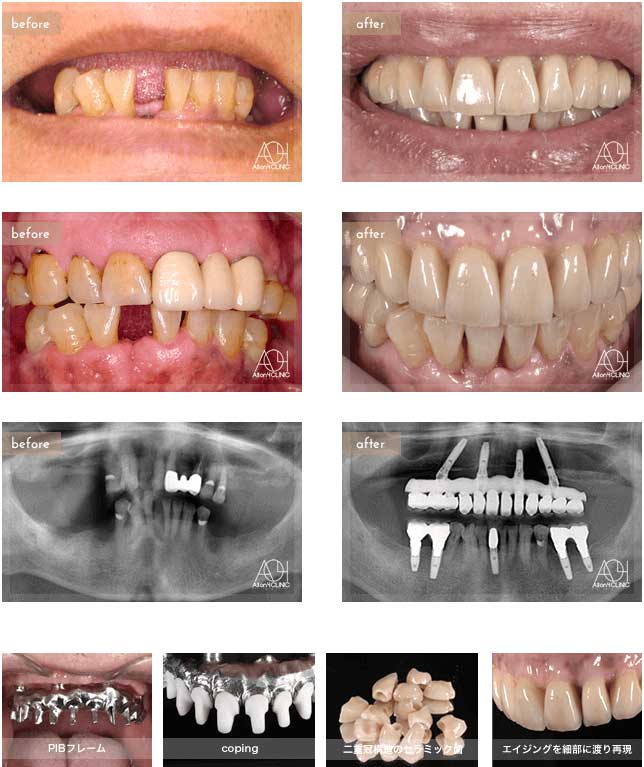

Treatment : All-on-4 non gum

- Upper All-on-4

- Lower implant

Age : 42 Sex : 女 Y.R

| 主訴 | 歯がボロボロなのは分かっているが、時間的な余裕が無いことと歯科に対する恐怖心から、悪いままの状態を放置してしまった。人前でおもいっきり笑いたいので意を決して来院。 |

| 治療内容 | ガイデッドサージェリーにてインプラント埋入。歯槽骨が残っていたため歯冠形態のみ(ガム無し)の補綴 |

| 治療費(総額) | ¥3,500,000(税抜) 『モニター割引適用』 |

| リスク | 治療後の口腔管理が不適切な場合、埋入したインプラント周囲に感染・炎症を起こし、脱落する可能性がございます。 |